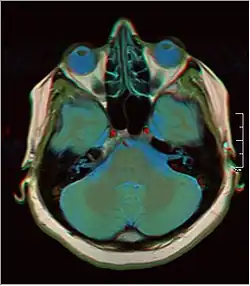

![]() Cross-sectional T1-weighted MRI of a healthy human brain acquired with an ultra high-field MR of 7 Tesla field strength | |

Magnetic resonance imaging of the brain uses magnetic resonance imaging (MRI) to produce high-quality two- or three-dimensional images of the brain, brainstem, and cerebellum without ionizing radiation (X-rays) or radioactive tracers.